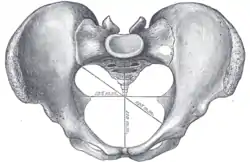

Diameters of superior aperture of lesser pelvis (female) | |

Diameters

The diameters or conjugates of the pelvis are measured at the pelvic inlet and outlet and as oblique diameters.

| Name | Description | Average measurement in female |

| Anteroposterior or conjugate diameter or conjugata vera | Extends from the upper margin of the pubic symphysis to the sacrococcygeal joint; | about 110 mm. |

| Transverse diameter | Extends across the greatest width of the superior aperture, from the middle of the brim on one side to the same point on the opposite; | about 135 mm. |

| Oblique diameter | Extends from the iliopectineal eminence of one side to the sacroiliac articulation of the opposite side; | about 125 mm. |

| Anatomical conjugate | Extends from the pubic symphysis to the promontory; | about 120 mm. |

| Diagonal conjugate | Extends from lower margin of the pubic symphysis to the sacral promontory; | about 130 mm. |

| Straight conjugate | Extends from the lower border of the pubic symphysis to the tip of coccyx. The coccyx can bend posteriorly and expand the diameter with 25 mm; | about 95 mm (+ 25 mm). |

| Median conjugate | Extends from the lower border of the pubic symphysis to the lower border of the sacrum; | about 115 mm. |